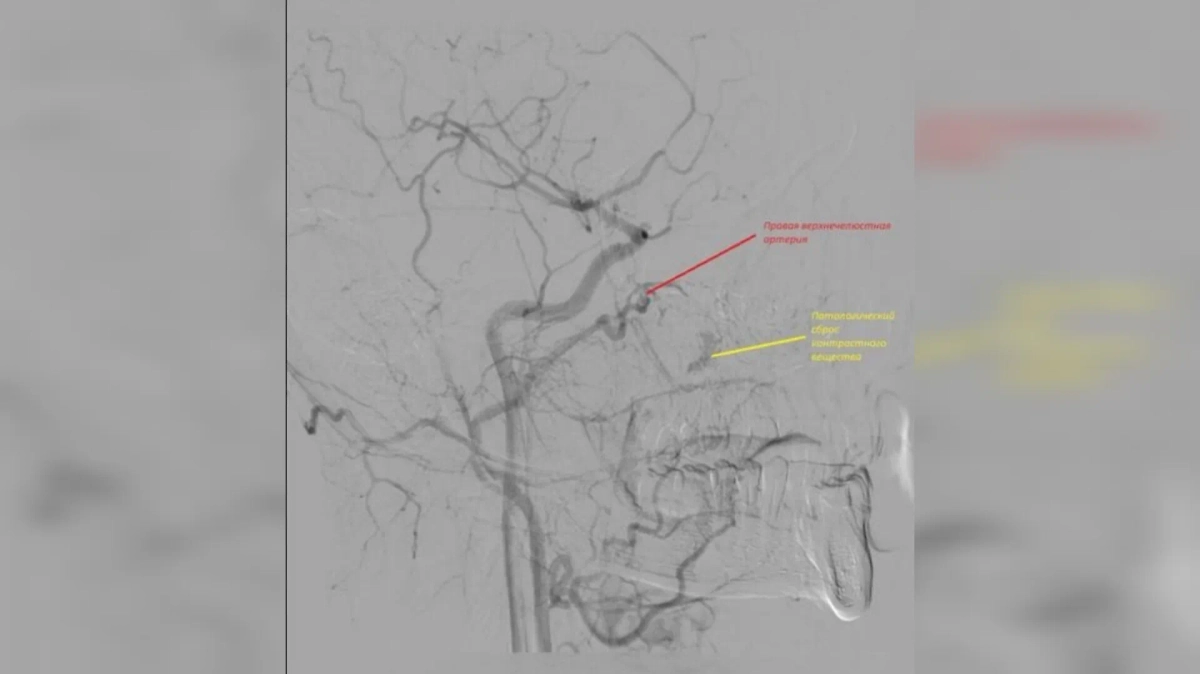

Врачи попытались остановить кровотечение с помощью носового тампона, однако поток крови лишь усиливался. В итоге медики прибегли к хирургическому вмешательству. Источник кровотечения они нашли в дистальных отделах правой верхнечелюстной артерии. После операции пациента выписали домой, больше его ничего не беспокоит.

Патологический сброс контрастного вещества (жёлтый). Фото © VK / Орловская областная клиническая больница